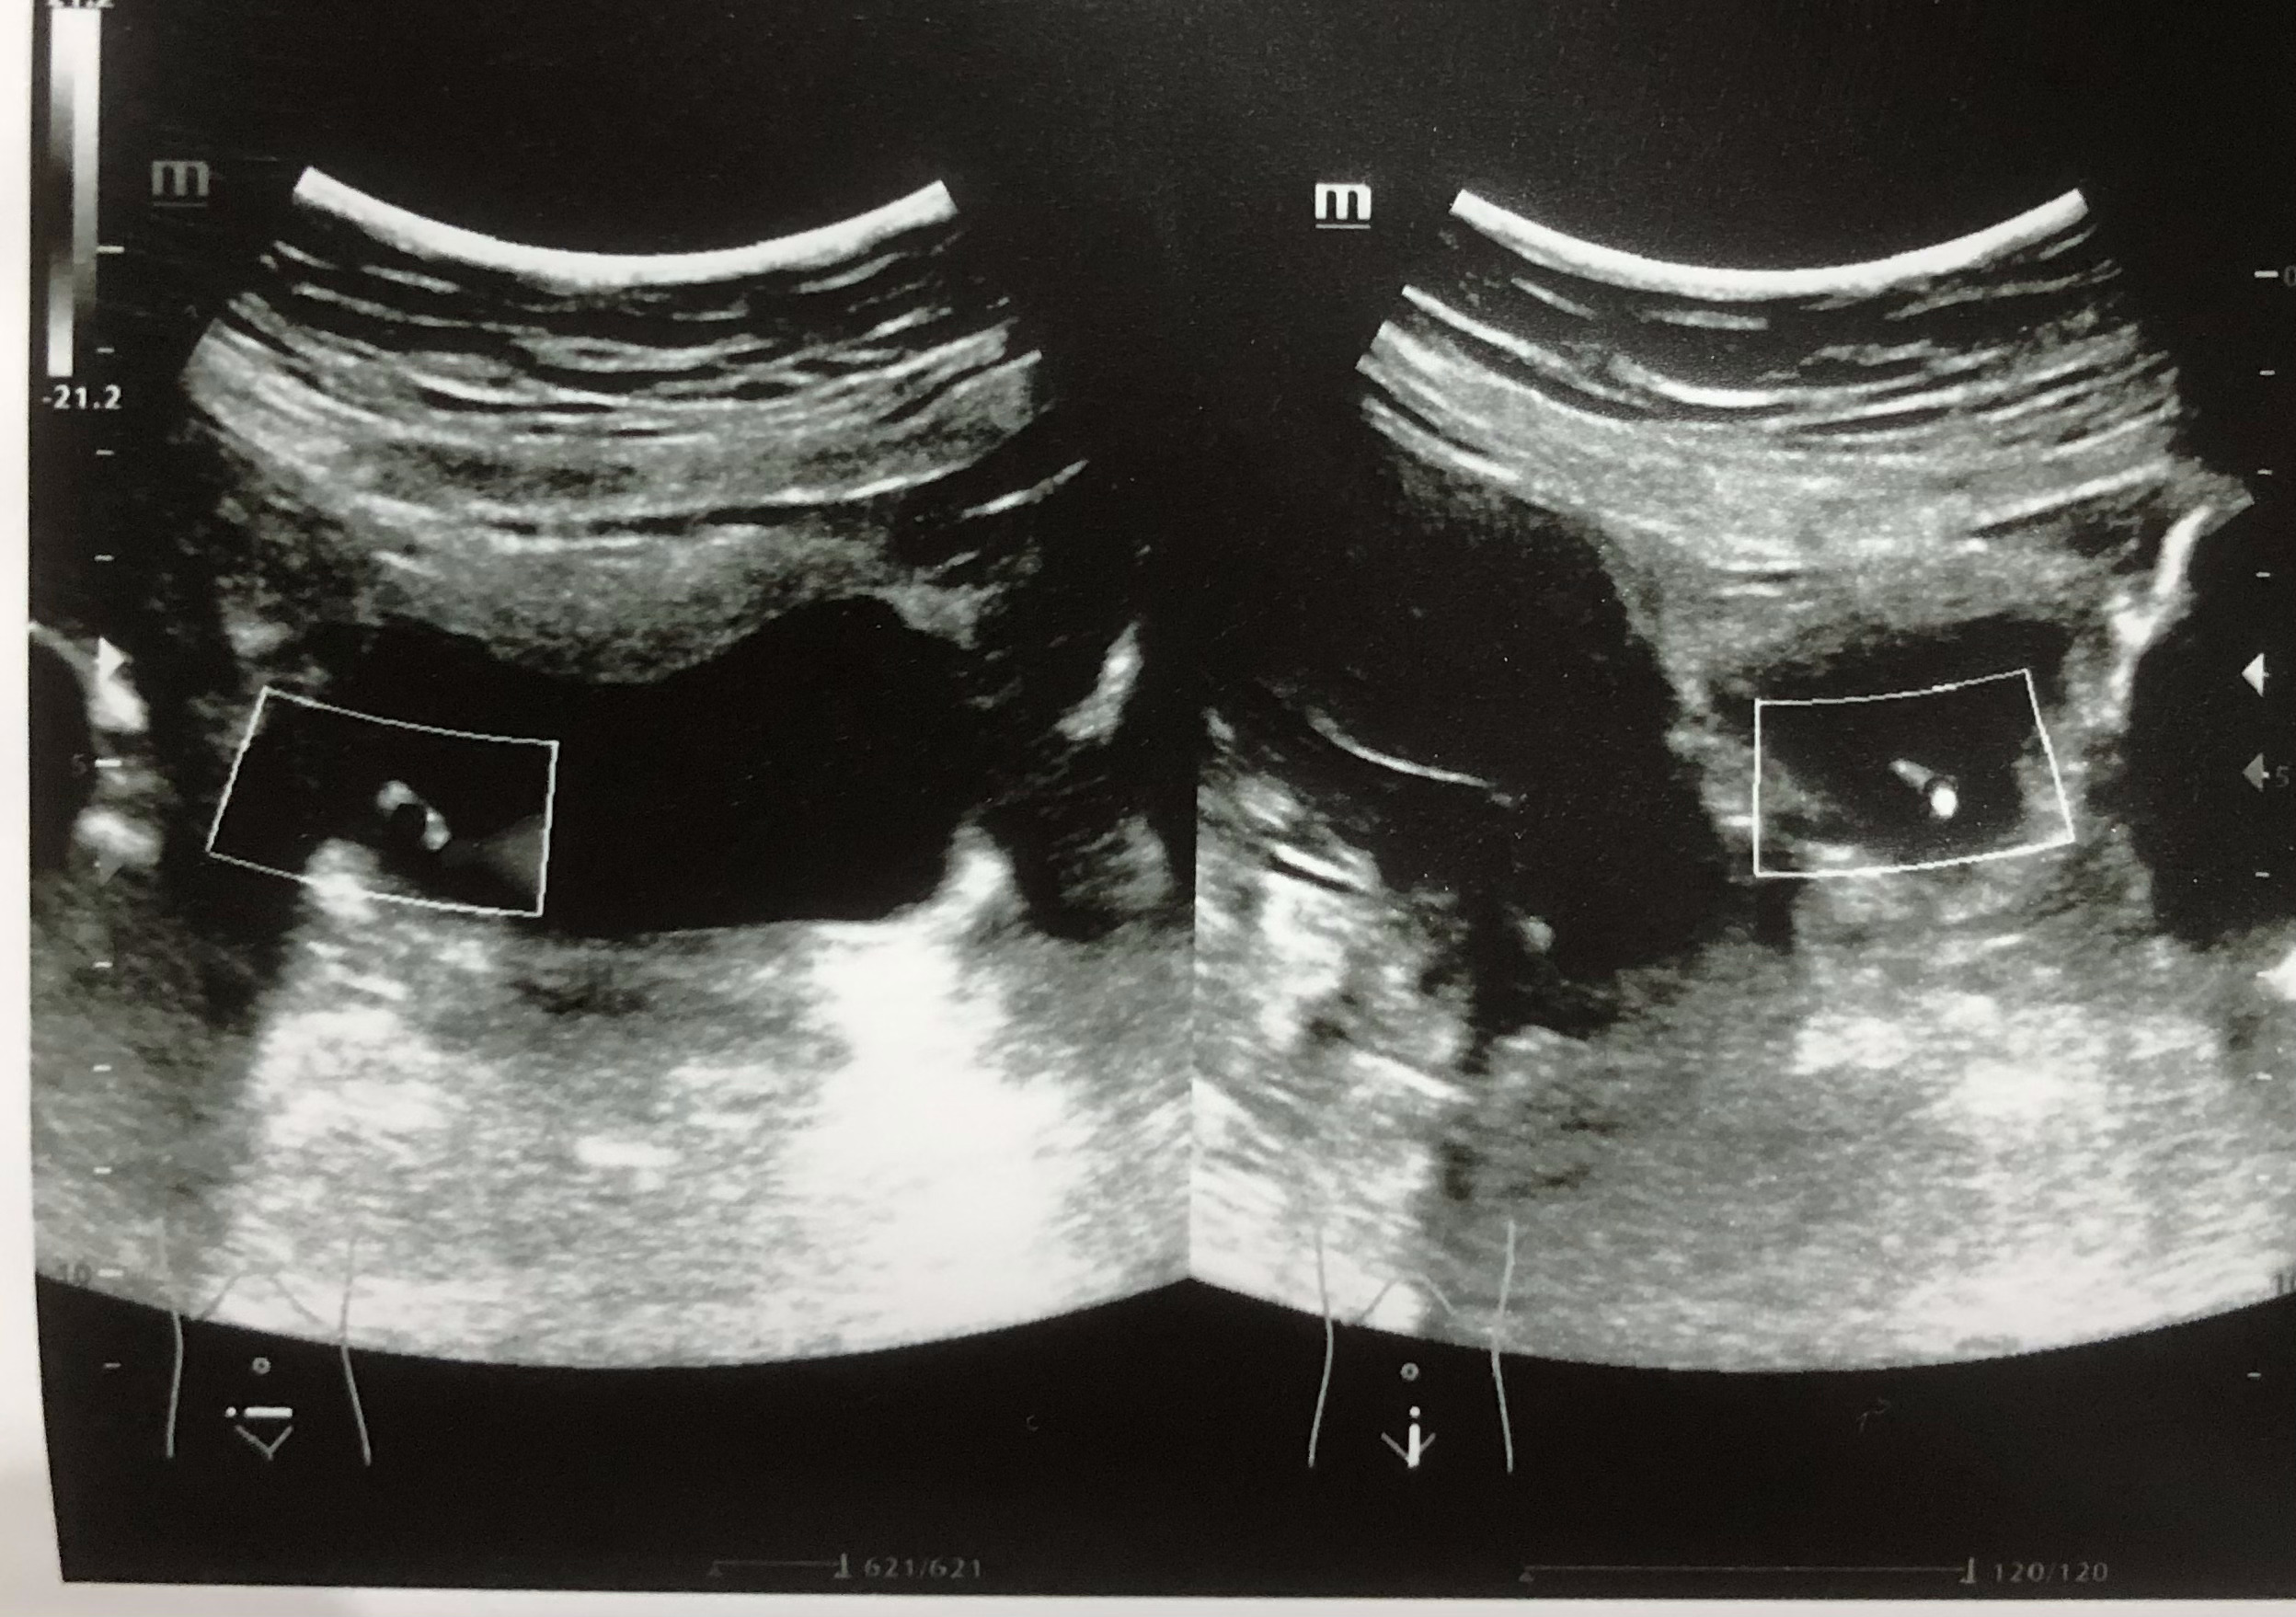

Se realiza ecografía renal donde se aprecia lesión hiperecogénica redondeada en pared inferior derecha de vejiga sin sombra posterior de 0,7 x 0,61 cm, que no se moviliza con cambios posturales de la paciente. Centelleo dudoso.